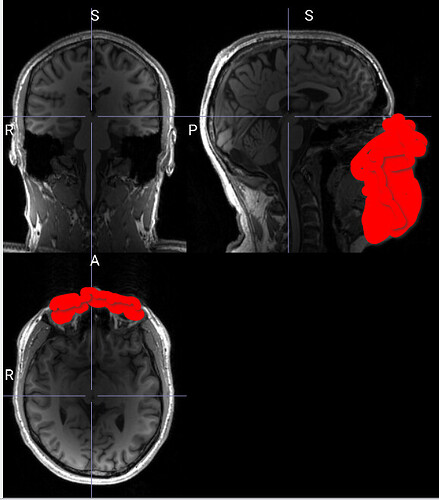

I checked my T1w images (they are not non-uniformity corrected by the scanner, but this shouldn’t be a problem?) and they look good:

However, the output was really bad (missing surfaces for a lot of brain regions and/or artifacts like surfaces out of the cortex and or pials that belong to the wrong hemisphere). I think that’s all due to the non-uniformity in my T1 images (see above, the occipital areas are brighter than the rest of the brain).

However, FS 7.1 underperformed due to intensity normalisation problems leading to the exclusion of a substantial part of the occipital cortex from the brain mask in 6 subjects (4 HCs and 2 T1D patients)

I ran fmriprep sucessfully on all my subjects with fs-no-reconall. I also checked all the brain masks and they look much better than the ones created by recon-all (i.e. even for the subjects for which I didn’t obtain any errors the brain masks from recon-all sometimes missed out smaller parts of the occipital lobe).